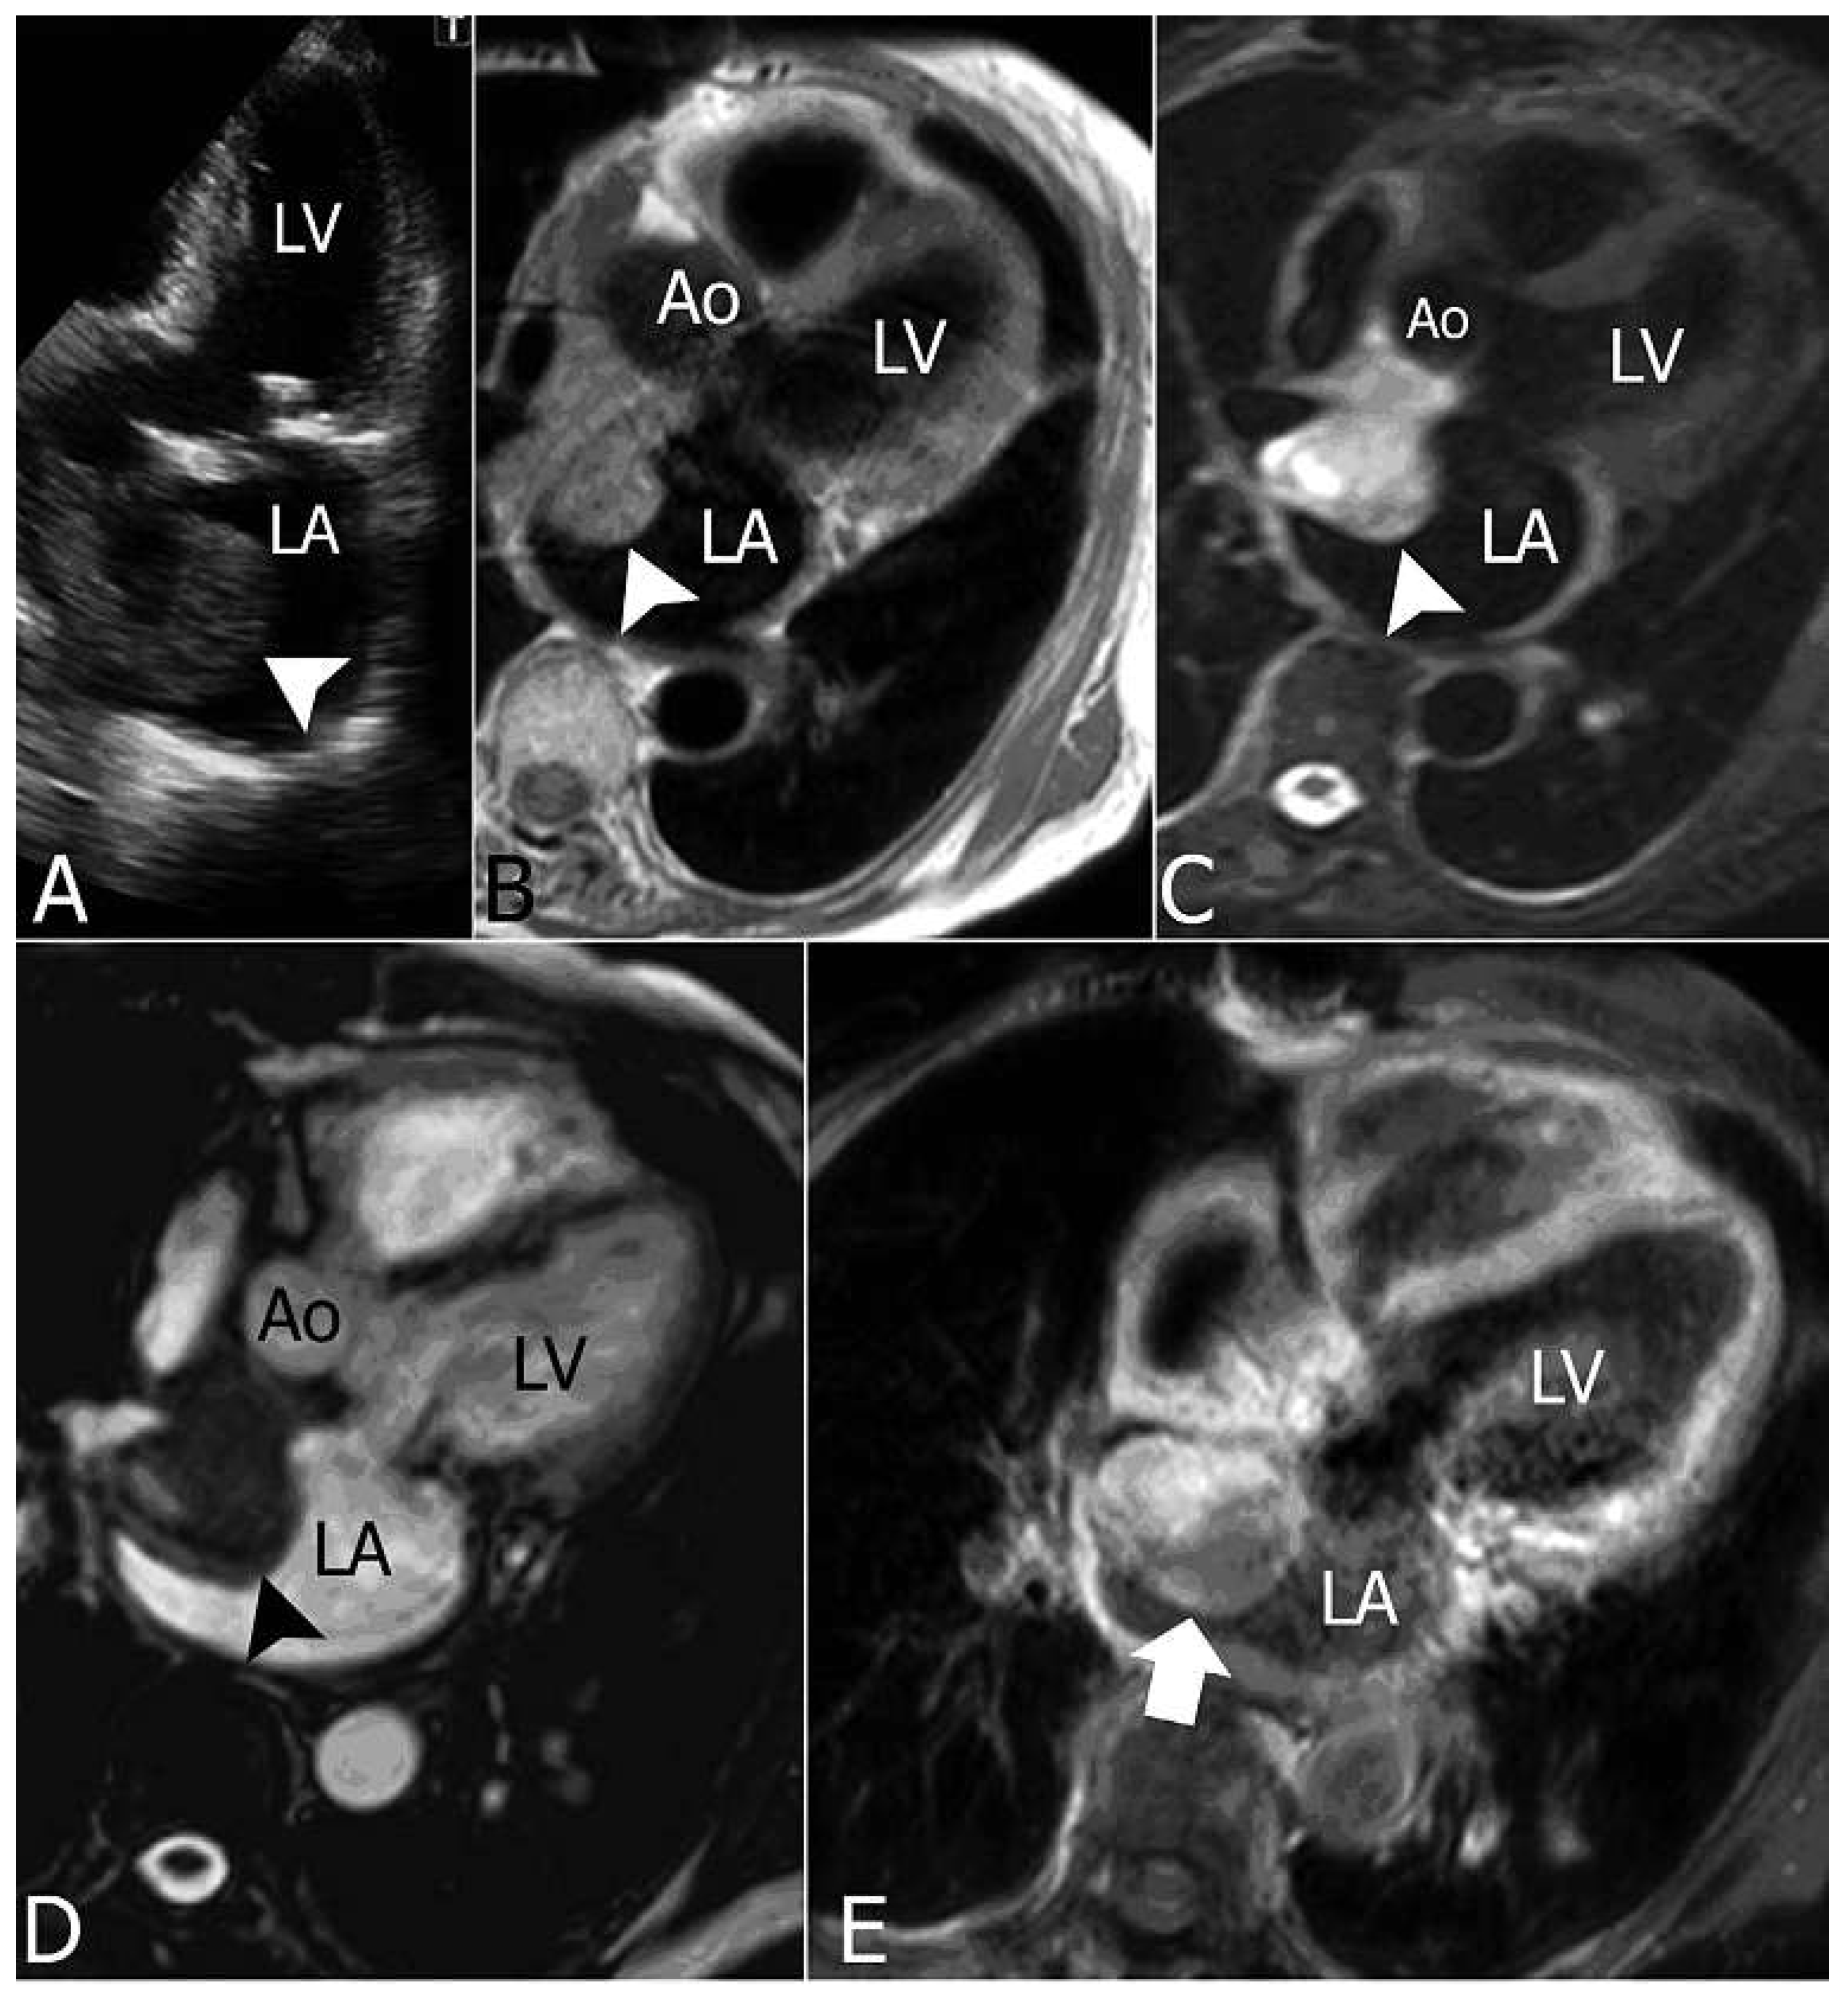

Transthoracic echocardiography showed local recurrence of the tumour in the left atrium, with a round-shaped lesion (39 × 39 mm) adherent to the roof and the upper part of the atrial septum (Figure 5).

Figure 5. Follow-up transthoracic echocardiography (A) showed local recurrence of the tumour in the LA with presence of a round-shaped lesion (39 × 39 mm) adherent to the roof and upper portion of the IAS. Cardiac MR (BD) confirms the presence in the LA (arrowheads) of solid and well defined tissue adherent to the atrial roof and upper portion of the IAS, extending anteriorly behind the aortic root, with a significative enhancement of the lesion (arrow) in the post-contrast scan (D). IAS = interatrial septum; Ao = aorta; LA = left atrium; LV = left ventricle; TTE = transthoracic echocardiography.